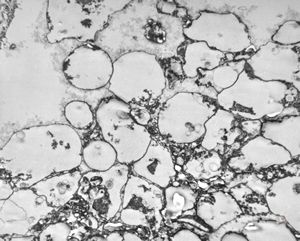

M,50y. | Pneumocystis carinii - lung